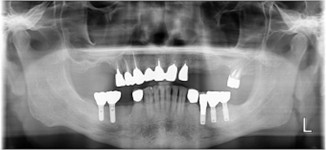

70代 女性

治療前

- 70代/女性

- 患者の具体的な症状

- 下顎の奥歯が義歯で噛みづらいため、インプラント治療を希望

- 検査方法

- コーンビームCT、レントゲン撮影

- 診断結果

- 左下6欠損

- 治療詳細

- 左下6インプラント埋入1本、骨造成なし、局所麻酔

- 通院回数

- 8回

- 治療期間

- 6か月